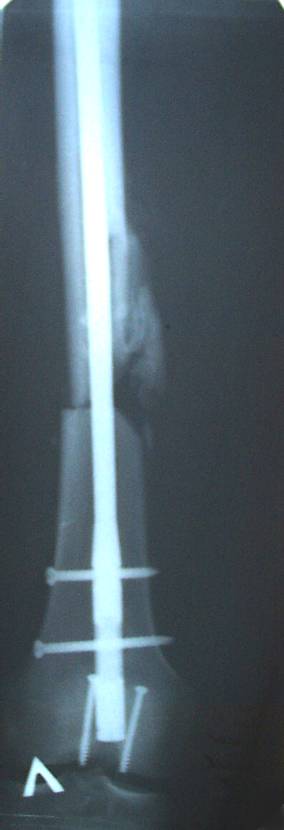

Уважаемый Сергей, избрав вариант DHS плюс ретроградный гвоздь Вы явно обезопасите себя от проблем, связанных с введением штифта через trochanteric fossa. Очень это может быть проблематично, Вы правы. Поэтому DHS плюс ретроградный гвоздь - спокойно выполнимый вариант, особенно в "чужом" отделении. Схожий свой случай из далёкого теперь уже 1999г. прилагаю, только вместо канюлированных винтов у Вас будет DHS (VHS). А если антеградный гвоздь - то только из тех, что предназначены к введению через верхушку вертела. И это тоже выполнимо, но сложнее. Мне так кажется.